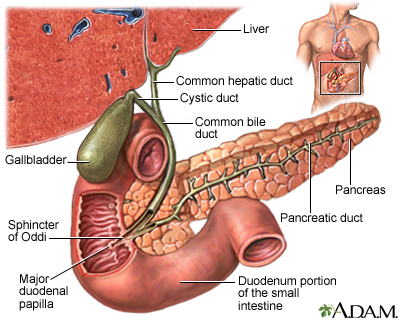

Bile and the Gallbladder

The formation of gallstones is a complex process that starts with bile, a fluid composed mostly of water, bile salts, lecithin (a type of phospholipid), and cholesterol. Most gallstones are formed from cholesterol.

- Bile is important for the digestion of fat. It is first produced by the liver and then secreted through tiny channels that eventually lead into a larger tube called the common bile duct, which leads to the small intestine.

- Only a small amount of bile drains directly into the small intestine, however. Most flows into the gallbladder through the

cystic duct

, which is a side branch off the common bile duct. This system of ducts through which bile flows is called thebiliary tree

.

- The gallbladder is a 3 to 4-inch (7 to 10 cm) sac with a muscular wall that is located under the liver. Here, most of the fluid is removed from the bile (about 2 to 5 cups, or 0.6 to 1.2 liters of bile gets produced by the liver in a day), leaving only a few tablespoons of concentrated bile.

- The gallbladder serves as a reservoir until bile is needed in the small intestine to digest fats. This need is signaled by a hormone called

cholecystokinin

, which is released when food enters the small intestine. - Cholecystokinin causes the gallbladder to contract and deliver bile into the intestine. The force of the contraction propels the bile down the common bile duct and into the small intestine, where it emulsifies (breaks down) fatty molecules.

- This part of the digestive process enables the emulsified fat, along with important fat-absorbable nutrients (such as vitamins A, D, E, and K), to pass through the intestinal lining and enter the bloodstream.